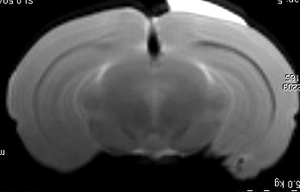

Hyperpolarization is a technology that enhances the signal from tracer molecules by a factor of 10,000-100,000.  This makes it possible to image the transport, uptake, and metabolism of dilute tracer molecular and metabolites with MRI.  Pyruvate (seen in images above) is a common metabolic probe used to assess rates of glycolytic fermentation in cancer through its conversion to lactate.  In the images above, a tumor-bearing mouse (left) shows high levels of pyruvate signal (center) in the large vessels, while high rates of lactate formation are seen within the tumor (right).